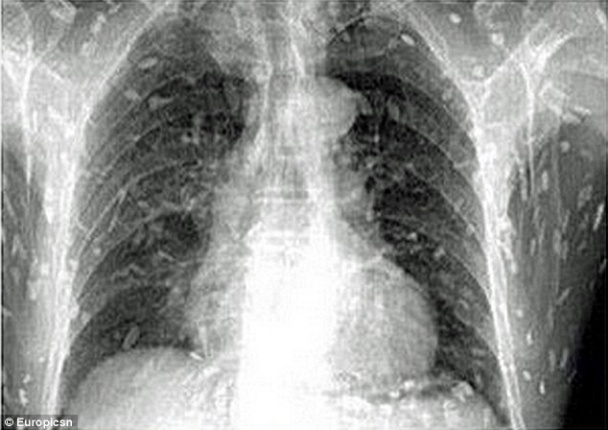

Рентген-снимки мужчины ужаснули врачей

В Китае в Гуанчжоу мужчина обратился в больницу с жалобами на сильные боли в животе и зуд кожи. После того как врачи получили рентген-снимки китайца, они ужаснулись: все тело мужчины было заражено солитером, сообщает ТСН.ua.Узнав, что пациент является большим любителем суши, врачи сделали вывод, что мужчина заразился червями-паразитами после употребления в пищу сашими. Исследования подтверждают, что употребление в пищу сырой или не достаточно хорошо доваренной рыбы может привести в результате к целому ряду паразитарных инфекций. Заражение червем-солитером возникает после попадания в организм личинок Diphyllobothrium, которые находятся в пресноводной рыбе, тем не менее, маринованной и копченой рыбы также могут содержатся личинки червей. Подобные случаи заражения все чаще встречаются в более развитых странах. Канадские врачи утверждают, что это неразрывно связано с растущей популярностью суши. Нэнси Крейг, автор исследования сделала вывод, что не только японские суши а также сашими могут стать источником заражения солитером, но и в принципе любые блюда из сырой либо маринованной рыбы. Читайте также: В Питере появился аппаратный LPG массаж Ученые: чай в пакетиках вреден для здоровья Ученые назвали самые эффективные диеты Доктор Инь из больницы в Гуанчжоу, куда попал зараженный китаец, заявил, что употребление сырой или полусырой пищи, загрязненной яйцами ленточных червей, в результате может привести к цистицеркозу, при которой взрослые черви попадают в кровь человека. В частности этот тип инфекционного заболевания является опасным для жизни человека, в том случае если он достигает головного мозга. | |

В Китае в Гуанчжоу мужчина обратился в больницу с жалобами на сильные боли в животе и зуд кожи. После того как врачи получили рентген-снимки китайца, они ужаснулись: все тело мужчины было заражено солитером, сообщает ТСН.ua.